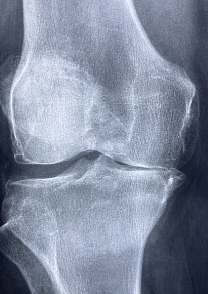

무릎 관절 통증 증상 원인 무릎 관절에 좋은 운동 및 음식 알아봐요. 관절은 뼈와 뼈 사이에 위치하며, 뼈가 서로 움직일 수 있도록 돕는 유연한 연결부입니다. 관절은 뼈의 움직임을 통제하고 충격을 흡수하는 역할을 하며, 인체의 움직임과 자세를 유지하는 데 중요한 역할을 합니다. 관절에는 다양한 종류가 있으며, 골관절, 연골관절, 다발성 연골관절 등이 있습니다. 관절에는 연골, 인대, 근육, 건초 등이 있으며, 이러한 부위들은 관절 기능의 원활한 유지를 위해 균형을 유지하고 있습니다. 관절은 일상적인 활동과 운동에 필수적이며, 체중 관리, 근력 강화 등의 생활 습관을 통해 건강한 관절을 유지할 수 있습니다.

무릎 관절 정보